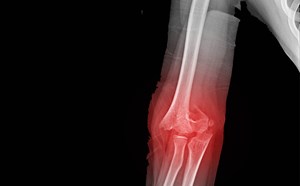

A 55-year-old helmeted male with a past medical history of hypertension, hyperlipidemia, and hypothyroidism, presented with left ankle pain and left leg pain after hitting black ice and falling while ...